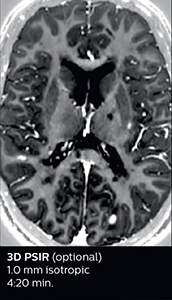

The abbreviated MS protocol for brain is only around 9 minutes, so in case of suspected multiple sclerosis, one or two more advanced sequences may be added, such as PSIR (phase sensitive inversion recovery) or susceptibility-weighted sequences to help us make more confident diagnoses in these inflammatory cases.

In this example, the optional 3D multishot susceptibility weighted sequence with 0.6 mm isotropic voxels is 2 lesions with a central vein sign (arrows) and one lesion with a phase-rim sign (arrowhead). The total scan time, including SmartBrain and axial PD/T2 3mm, is 11:10 min. and is 18:30 min. with the optional 3D PSIR and 3D SWI multishot included.

“We used to have long examination times for certain types of patients, a few lasting more than 40 minutes,” says Dr. Savatovsky. “What is remarkable, is that now all these examinations are below 30 minutes, which opens up opportunity to add more sequences when needed. It’s really hard to keep a patient for more than 40 minutes in the scanner, but because we have now cut scan times by at least 10 minutes, we can add more sequences without making the exam too long. And this is where the new system helps us make a difference. Examples include our examinations for informing brain tumor classification or giant cell arteritis workup, or for intracranial wall imaging – so in patients where we need several advanced sequences or high resolution sequences.” “We added three additional sequences in our brain neoplasm classification exam: a 3D SWI sequence, APT and ASL on top of 3D morphologic sequences, an isotropic DSC (dynamic susceptibility contrast) and multivoxel spectroscopy. I think that in patients that need a classification for brain mass, for example, we can provide a more detailed and confident diagnosis than before, allowing the clinicians to decide for either a medical workup if no tumor is suspected, or for neurosurgery as soon as possible if a neoplasm is suspected.” “In multiple sclerosis patients, we increasingly include a multishot susceptibility sequence [3] in our routine cases, thanks to the shorter scan times. Our abbreviated MS protocol for brain is around 8 to 9 minutes, so we can ask for one or two additional sequences to visualize the central veins, or to get an additional contrast to better depict posterior fossa lesions. In cases of white matter lesions of unknown significance on FLAIR images, for example when we see high signal hyperintensities in the brain, we can add on more advanced sequences such as PSIR (phase sensitive inversion recovery) or susceptibility-weighted sequences to help us in distinguishing between MS and nonspecific or vascular abnormalities in these inflammatory cases.”